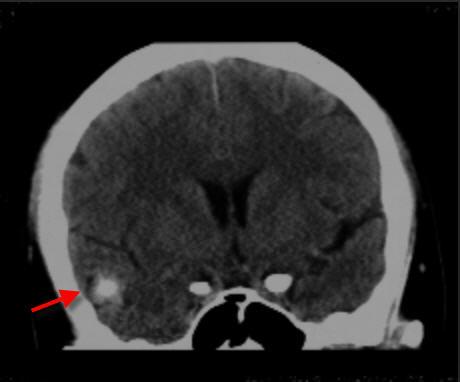

2019年2月25日头颅平扫+图像重组CT片示:左额部头皮软组织肿胀,右侧颞叶见类圆形高密度影,中线结构居中。

2019年3月14日头颅平扫+图像重组CT片示:左额部头皮软组织肿胀已恢复,右侧颞叶见类圆形高密度影,较前无动态变化。

2019年4月12日本院头颅平扫+图像重组CT片示:右侧颞叶见类圆形高密度影,较前无动态变化。

现本院审阅许某受伤当天影像学资料显示左额部头皮软组织肿胀,右侧颞叶见类圆形高密度影,中线结构居中;伤后3周复查头颅CT显示左额部头皮软组织肿胀已恢复,右侧颞叶见类圆形高密度影,较前无动态变化;伤后1月余复查头颅MRI显示右侧颞叶见类圆形异常信号影,呈T1高信号,FLAIR周边高、中央低信号,随访无动态变化;近期本院复查头颅CT显示右侧颞叶见类圆形高密度影,较前无动态变化。综上,分析其右侧颞叶类圆形高密度影,形态、密度等随时间变化无动态改变,不符合外伤后脑出血灶的演变规律,考虑系自身占位性病变(右侧颞叶海绵状血管瘤),与本次头部外伤之间存在因果关系的依据不足。

受伤当天头颅CT片显示右侧颞叶见类圆形高密度影

受伤当日头颅CT片显示右侧颞叶见类圆形高密度影 4月12日头颅CT片未呈现动态变化